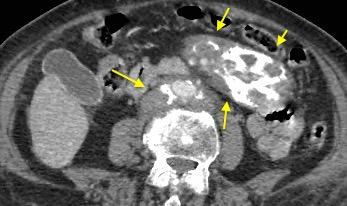

Ganglios retroperitoneales (flechas negras)

germinales del testículo izquierdo Nódulos pulmonares múltiples. (flechas verdes). Ganglios paratraqueales. (flechas amarillas). Dudoso ensanchamiento retrocrural (flechas negras)

Panda A et al. “Straddling Across Boundaries”. Thoracoabdominal Lesions: Spectrum and Pattern Approach. Curr Probl Diagn Radiol, 2015